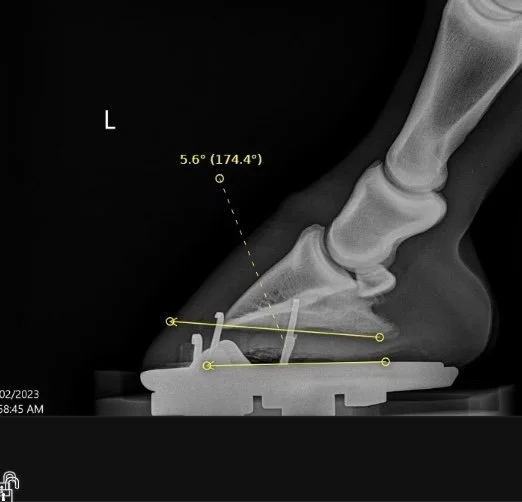

Digital radiographs (X-rays) if required – to assess internal structures and alignment

X-ray guided feedback on hoof-pastern axis